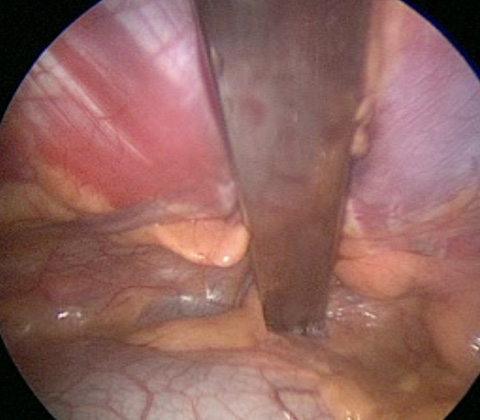

Intraoperative image of bar in place at deepest point of pectus excavatum lifting and correcting chest deformity

The Nuss or MIRPE operation is a keyhole operation involving insertion of a metal bar behind the breastbone to correct the pectus excavatum.